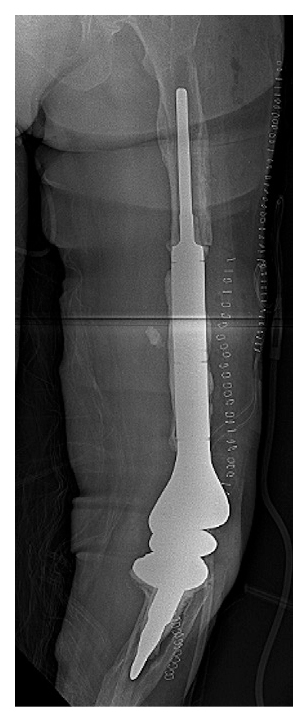

She developed severe gastric symptoms after several months and discontinued oral antibiotics, after which bilateral knee pain recurred. Aspiration revealed persistence of staphylococcal PJI. The patient again underwent staged bilateral surgery, with removal of the right knee spacer and placement of another articulating spacer. On the left side a complex knee revision was undertaken with the trauma service due to concerns for persisting infection; the cephalomedullary nail, remaining lateral femoral plate, and part of the femoral diaphysis were removed. A longer distal femoral replacement with a larger intercalary segment was performed (Figure 3), but 2 months later a lateral drainage developed through an old incision site, necessitating both-component revision with assistance from plastic surgery. Soft tissue coverage with a medial gastrocnemius flap and skin coverage with a simultaneous medial fasciocutaneous flap were achieved.

Figure 3: Postoperative lateral radiograph of left knee after revision and cephalomedullary nail and complete femoral plate removal.